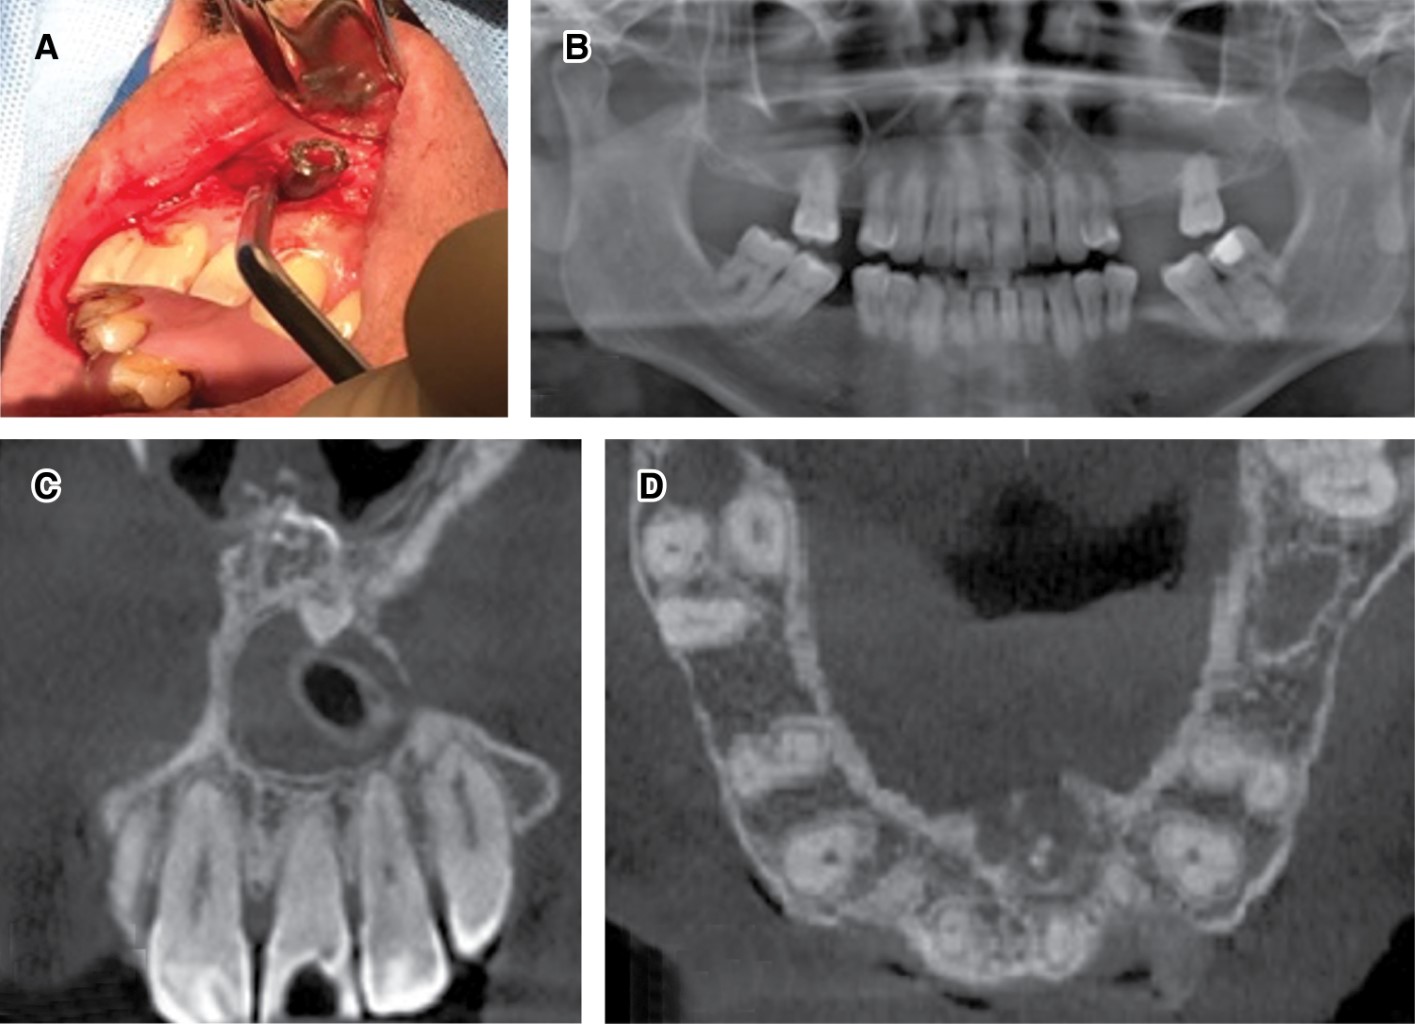

Paciente de género masculino de 43 años de edad consulta por aumento de volumen en paladar. Sin antecedentes sistémicos, relata dolor moderado, intermitente, localizado junto a sensación opresiva en sector anterosuperior maxilar, con tiempo de evolución desconocido. Al examen clínico se observa tumoración en fondo de vestíbulo y paladar, extendida desde 2.2 hasta 1.1, de forma redondeada, consistencia firme, cubierta por mucosa normal, doloroso a la palpación y de límites definidos. Los dientes involucrados presentaban caries, pero se encontraban vitales a las pruebas endodónticas y no presentaban movilidad ni desplazamiento (Figura 1A).

En una primera instancia, se observó radiográficamente presencia de lesión radiolúcida de gran tamaño. Sin embargo, se observó integridad de espacios periodontales en los dientes comprometidos, por lo que se solicitó complementar con ortopantomografía y CBCT, donde se encontró una lesión osteolítica circunscrita, bien delimitada con márgenes corticalizados en relación con raíces dentarias de dientes 1.1 a 2.2, confirmando la presencia de lesión quística en zona maxilar anterosuperior asociada a la existencia de diente supernumerario invertido de localización buconasal con la corona proyectada hacia la cavidad nasal y la raíz orientada a la cavidad oral, con diámetros de 2.5 × 2.0 × 1.9 cm. Se evidenció además expansión de corticales óseas vestibular y palatina, generando un desplazamiento del conducto nasopalatino, sin compromiso de raíces de dientes vecinos (Figura 1B).

Posterior a consentimiento informado, se realiza biopsia incisional bajo anestesia local, donde se procede a instalar una cánula de descompresión con el objetivo de disminuir el tamaño de la lesión y se indicó aseo con clorhexidina al 0.12% tres veces al día con seguimiento radiográfico a los seis meses (Figura 2A). Con hipótesis diagnóstica de tumor odontogénico adenomatoide, las muestras obtenidas fueron enviadas a estudio histopatológico, el cual mostró una membrana quística con revestimiento epitelial escamoso no queratinizado, de pocas capas, focos de calcificaciones distróficas siendo características sugestivas de quiste dentígero. Tras seis meses de la intervención se realizó una nueva evaluación clínica e imagenológica, donde el paciente relató disminución del tamaño de la lesión y cese de sintomatología opresiva en relación con el sector anatómico comprometido, observándose radiográficamente una disminución del tamaño de la lesión quística en sector anterosuperior con un diámetro de 1.4 × 1.7 × 1.5 cm asociada a la presencia de cánula de descompresión en su espesor (Figura 2B-D).